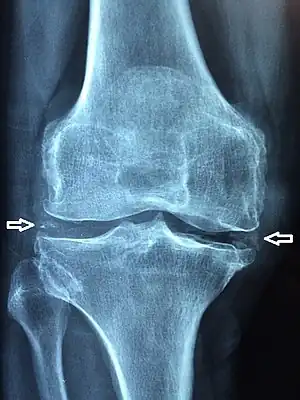

The disease is defined by the presence of joint inflammation and CPPD crystals within the joint. The crystals are usually detected by imaging or joint fluid analysis. X-ray, CT, or other imaging usually shows accumulation of calcium within the joint cartilage, known as chondrocalcinosis. There can also be findings of osteoarthritis.[12][9] The white blood cell count is often raised.[9]

Medical imaging, consisting of x-ray, CT, MRI, or ultrasound may detect chondrocalcinosis within the affected joint, indicating a substantial amount of calcium crystal deposition within the cartilage or ligaments.[13] Ultrasound is a reliable method to diagnose CPPD.[14] Using ultrasound, chondrocalcinosis may be depicted as echogenic foci with no acoustic shadow within the hyaline cartilage[15] or fibrocartilage.[14] By x-ray, CPPD can appear similar to other diseases such as ankylosing spondylitis and gout.[13][9]